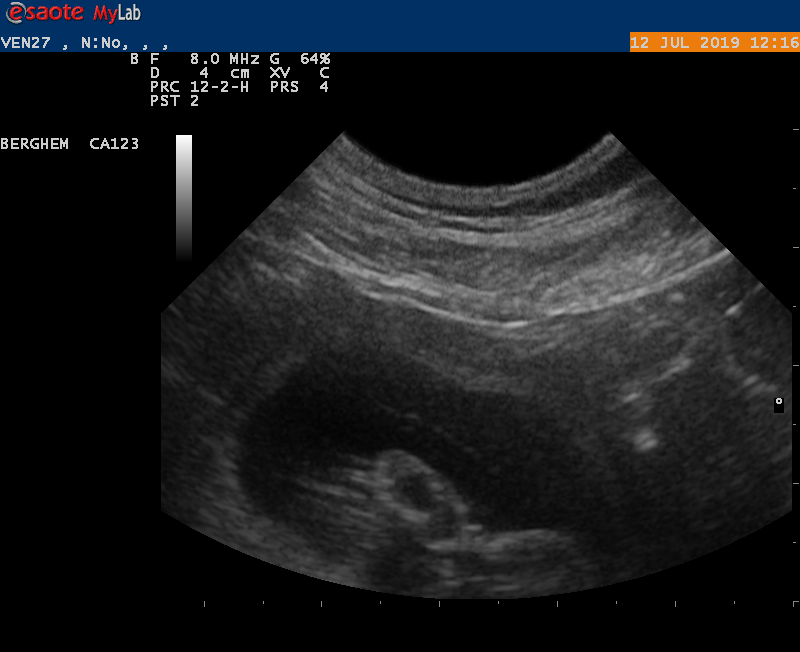

Juli 2019

We zijn met Earke bij de dierenarts geweest voor een echo en er zijn vruchtjes gezien. Heel mooi nieuws. Als alles goed blijft gaan kunnen we rond 17 augustus pups verwachten van Earke en Abe.